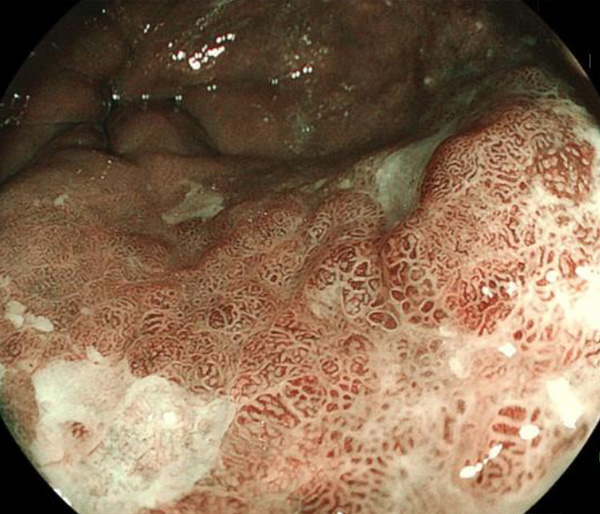

2026年1月24日開催の第19回研究会でご提示した検討症例です。 (画像をクリックすると拡大します)

2025年7月19日開催の第18回研究会でご提示した検討症例です。 (画像をクリックすると拡大します)

2025年1月11日開催の第17回研究会でご提示した検討症例です。 (画像をクリックすると拡大します)

2024年6月29日開催の第16回研究会でご提示した検討症例です。 (画像をクリックすると拡大します)

2024年1月6日開催の第15回研究会でご提示した検討症例です。 (画像をクリックすると拡大します)

2023年7月1日開催の第14回研究会でご提示した検討症例です。 (画像をクリックすると拡大します)

2023年1月21日開催の第13回研究会でご提示した検討症例です。 (画像をクリックすると拡大します)

2022年7月2日開催の第12回研究会でご提示した検討症例です。 (画像をクリックすると拡大します)

2022年1月22日開催の第11回研究会でご提示した検討症例です。 (画像をクリックすると拡大します)

2021年6月26日開催の第10回研究会でご提示した検討症例です。 (画像をクリックすると拡大します)

2021年1月23日開催の第9回研究会でご提示した検討症例です。 (画像をクリックすると拡大します)

2020年1月25日開催の第8回研究会でご提示した検討症例です。 (画像をクリックすると拡大します)

2019年1月12日開催の第6回研究会でご提示した検討症例です。 (画像をクリックすると拡大します)

2018年6月30日開催の第5回研究会でご提示した検討症例です。 (画像をクリックすると拡大します)

2017年7月15日開催の第3回研究会でご提示した検討症例です。 (画像をクリックすると拡大します)

2017年1月7日開催の第2回研究会でご提示した検討症例です。 (画像をクリックすると拡大します)

2016年6月4日開催の第1回研究会でご提示した検討症例です。 (画像をクリックすると拡大します)